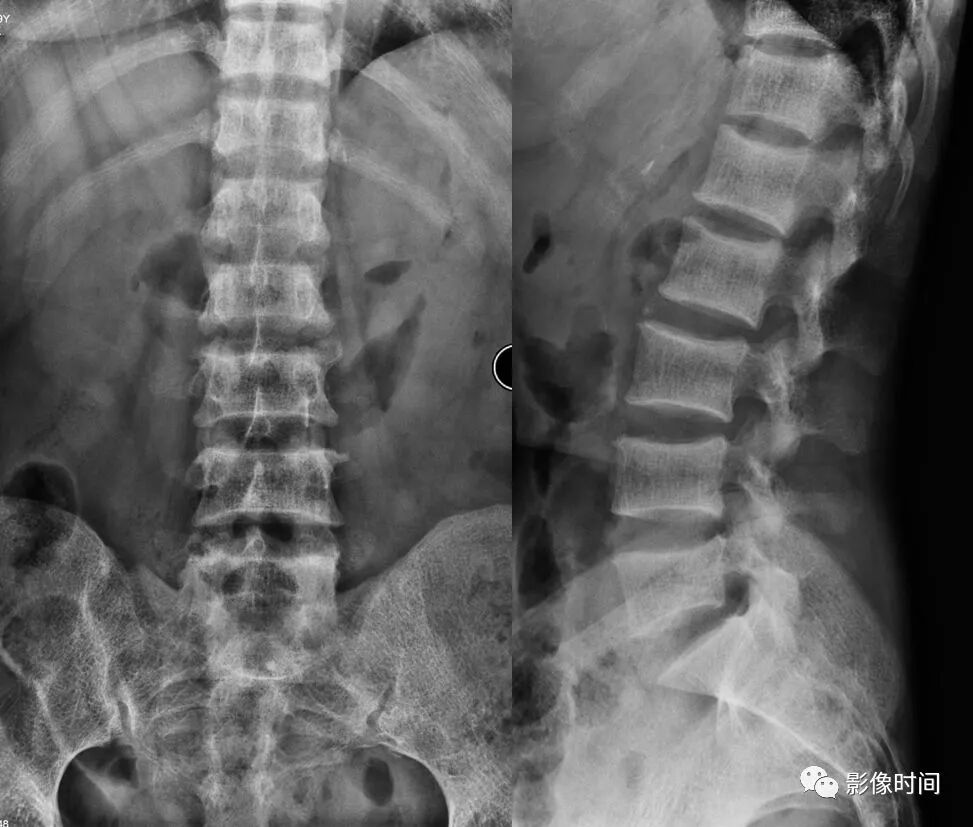

椎体夹心饼征:在X线平片上,胸腰椎椎体上、下缘终板各形成一条硬化带,每个椎体中心可见一条透明带,相互并行的硬化带和透明带与英式橄榄球衫(rugby sweater)上的条纹类似,西方学者称之为橄榄球衫椎体(rugger jersey spine)。这种两条硬化带中夹一条透明带的表现与中国的夹心饼亦相似,国内学者称之为夹心饼征。椎体终板上下缘的硬化带代表过多的骨样物质沉积,虽然它们的骨化并不充分,但这些骨样组织与正常椎体相比密度增加,在Ⅹ线照片上显示为不透光性,常为慢性肾衰竭所致